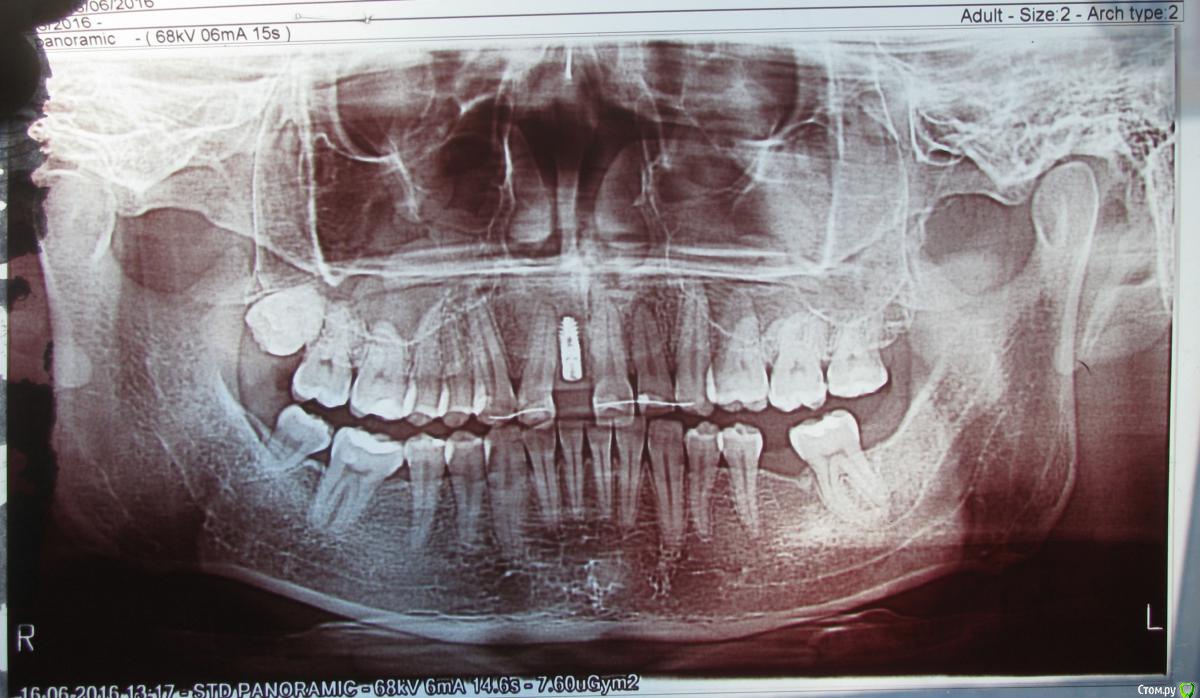

Scander Опубликовано 18 января, 2017 Автор Поделиться Опубликовано 18 января, 2017 (изменено) Здравствуйте. Забрал снимок. Ситуация у меня осложняется тем, что деньги за лечение уже уплачены. Дело происходит в клинике ............ Изготовленная коронка при посадке на абатмент (стандартный) ощущается дискомфортно - полного смыкания жевательных зубов нет. До этого на ортодонтической дуге висел декоративный зуб полное смыкание челюстей было возможно. На данный момент врач обтачивает изготовленную коронку. При этом она всячески демонстрирует свое недовольство, утверждая, что мне вовсе не следовало ставить имплант, а нужно было делать мостовидный протез. Когда речь заходит о том, что, возможно, следовало заказывать индивидуальный абатмент - она заявляет, что для этого не было показаний. Предлагает стачивать нижние зубы, чтобы они не мешали. Я категорически против этого. Пока взяли небольшой тайм-аут. Изменено 19 января, 2017 пользователем IvanK Ссылка на комментарий

Scander Опубликовано 20 января, 2017 Автор Поделиться Опубликовано 20 января, 2017 Меняйте врача. Совет,проверенный временем. И выложите снимок с парой фотографий, подумаем над альтернативой Здравствуйте, снимок выложен. Ссылка на комментарий

Scander Опубликовано 20 января, 2017 Автор Поделиться Опубликовано 20 января, 2017 Если кто-то все же решит помочь информацией, задам еще один вопрос:протезист утверждает, что нельзя слишком сильно истончать коронку (диоксид циркония) и предлагает стачивать нижние зубы, чтобы достичь нормального смыкания жевательных зубов - в этой ситуации, было бы более оправданным использование индивидуального абатмента? Ссылка на комментарий